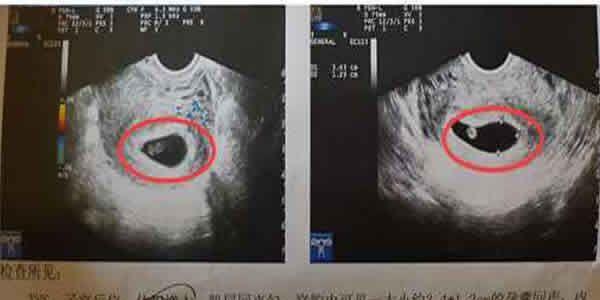

许多准妈妈说,孕囊形状能够看得出胎宝宝男孩女孩。一般说来,假如胎囊的样子像四季豆,或是是呈长条形的,则怀起男孩子的概率大;而假如胎囊是椭圆型或环形的,那麼很可能便是个女宝了。

实际上,胎囊的样子是由其支撑力及其其可屈伸的室内空间来决策的。假如妈妈的子宫形状较为标准,胎囊着床后,绝大部分是环形或椭圆型。假如妈妈的子宫不太标准,或是子宫内有子宫肌瘤,当胎囊着床后,样子便随着产生变化。

孕妈妈们的胎囊看起来样子有所区别与胎宝宝性别没有关系。一般生长发育不错的胎囊是圆扁型的,可是有时候胎囊会随宫腔内的样子而拉长。胎囊的样子由其支撑力和含羊水流量决策的,会自主更改样子。那样,怀孕日数不一样,见到的胎囊也很有可能不一样。因而根据孕囊形状测男女不是靠谱的。